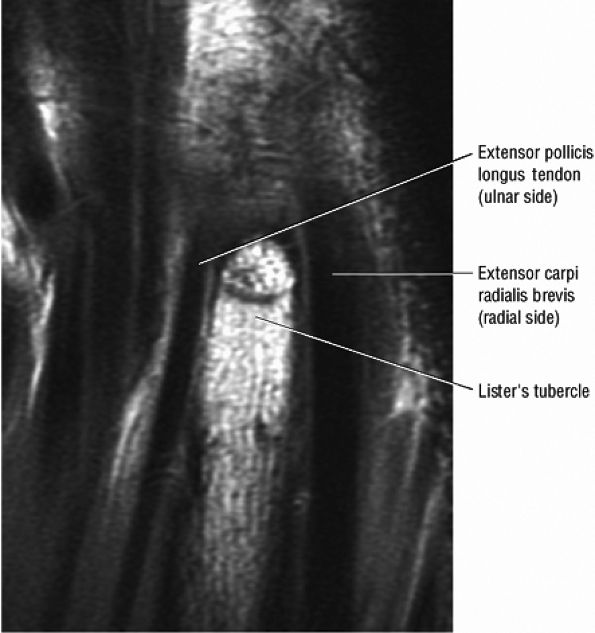

On dorsal images through the carpus, the interosseous ligaments of the distal carpal row can be defined. Dorsally, the obliquely oriented extensor digiti minimi tendon on the ulnar side of the triquetrum and the extensor carpi radialis longus tendon are seen. Lister's tubercle, which contains fatty marrow, is situated between and separates the ulnar aspect of the extensor pollicis longus from the radial aspect of the extensor carpi radialis brevis. The dorsal interossei muscles are demonstrated between the midcarpal shafts.

FIGURE 10.58 ● Lister's tubercle (dorsal tubercle) of the distal radius on a coronal PD FSE image. Lister's tubercle functions as a pulley for the extensor pollicis longus.